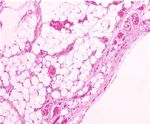

The removed mass’s dimensions were 5 × 5 × 8 cm, and               exceeds 4 cm [5, 10]. Multiple lesions are seen in approxi-

its weight was 68 grams (Figure 5). Histological examination           mately 70-80% of cases, and 5% of these are familiar but with

showed mature adipose tissue with a vaguely lobular archi-             an unclear genetic pattern [5]. A recent study suggests an

tecture, due to areas of excess fibrin deposition in the stroma         involvement of chromosome 13 in angiolipomas [11]. Clini-

(Figure 6(a)). Additionally, in a few subcapsular areas, there         cally, the encapsulated/noninfiltrative angiolipoma presents

were evident small groups of tiny thin-walled hyperplastic             as a subcutaneous nodule: the lesions are commonly multi-

vascular vessels, most of which exhibited the formation of             ple, typically firm, tender to palpation but often painful,

fibrous thrombi in their lumens (Figure 6(b)). These mor-               and rarely associated with overlying skin changes [2, 5, 9,

phological characteristics were compatible with the diagnosis          10]. Pain and associated neuropathies are secondary to vascular

of angiolipoma [6].                                                    engorgement and edema that can lead to compression of the